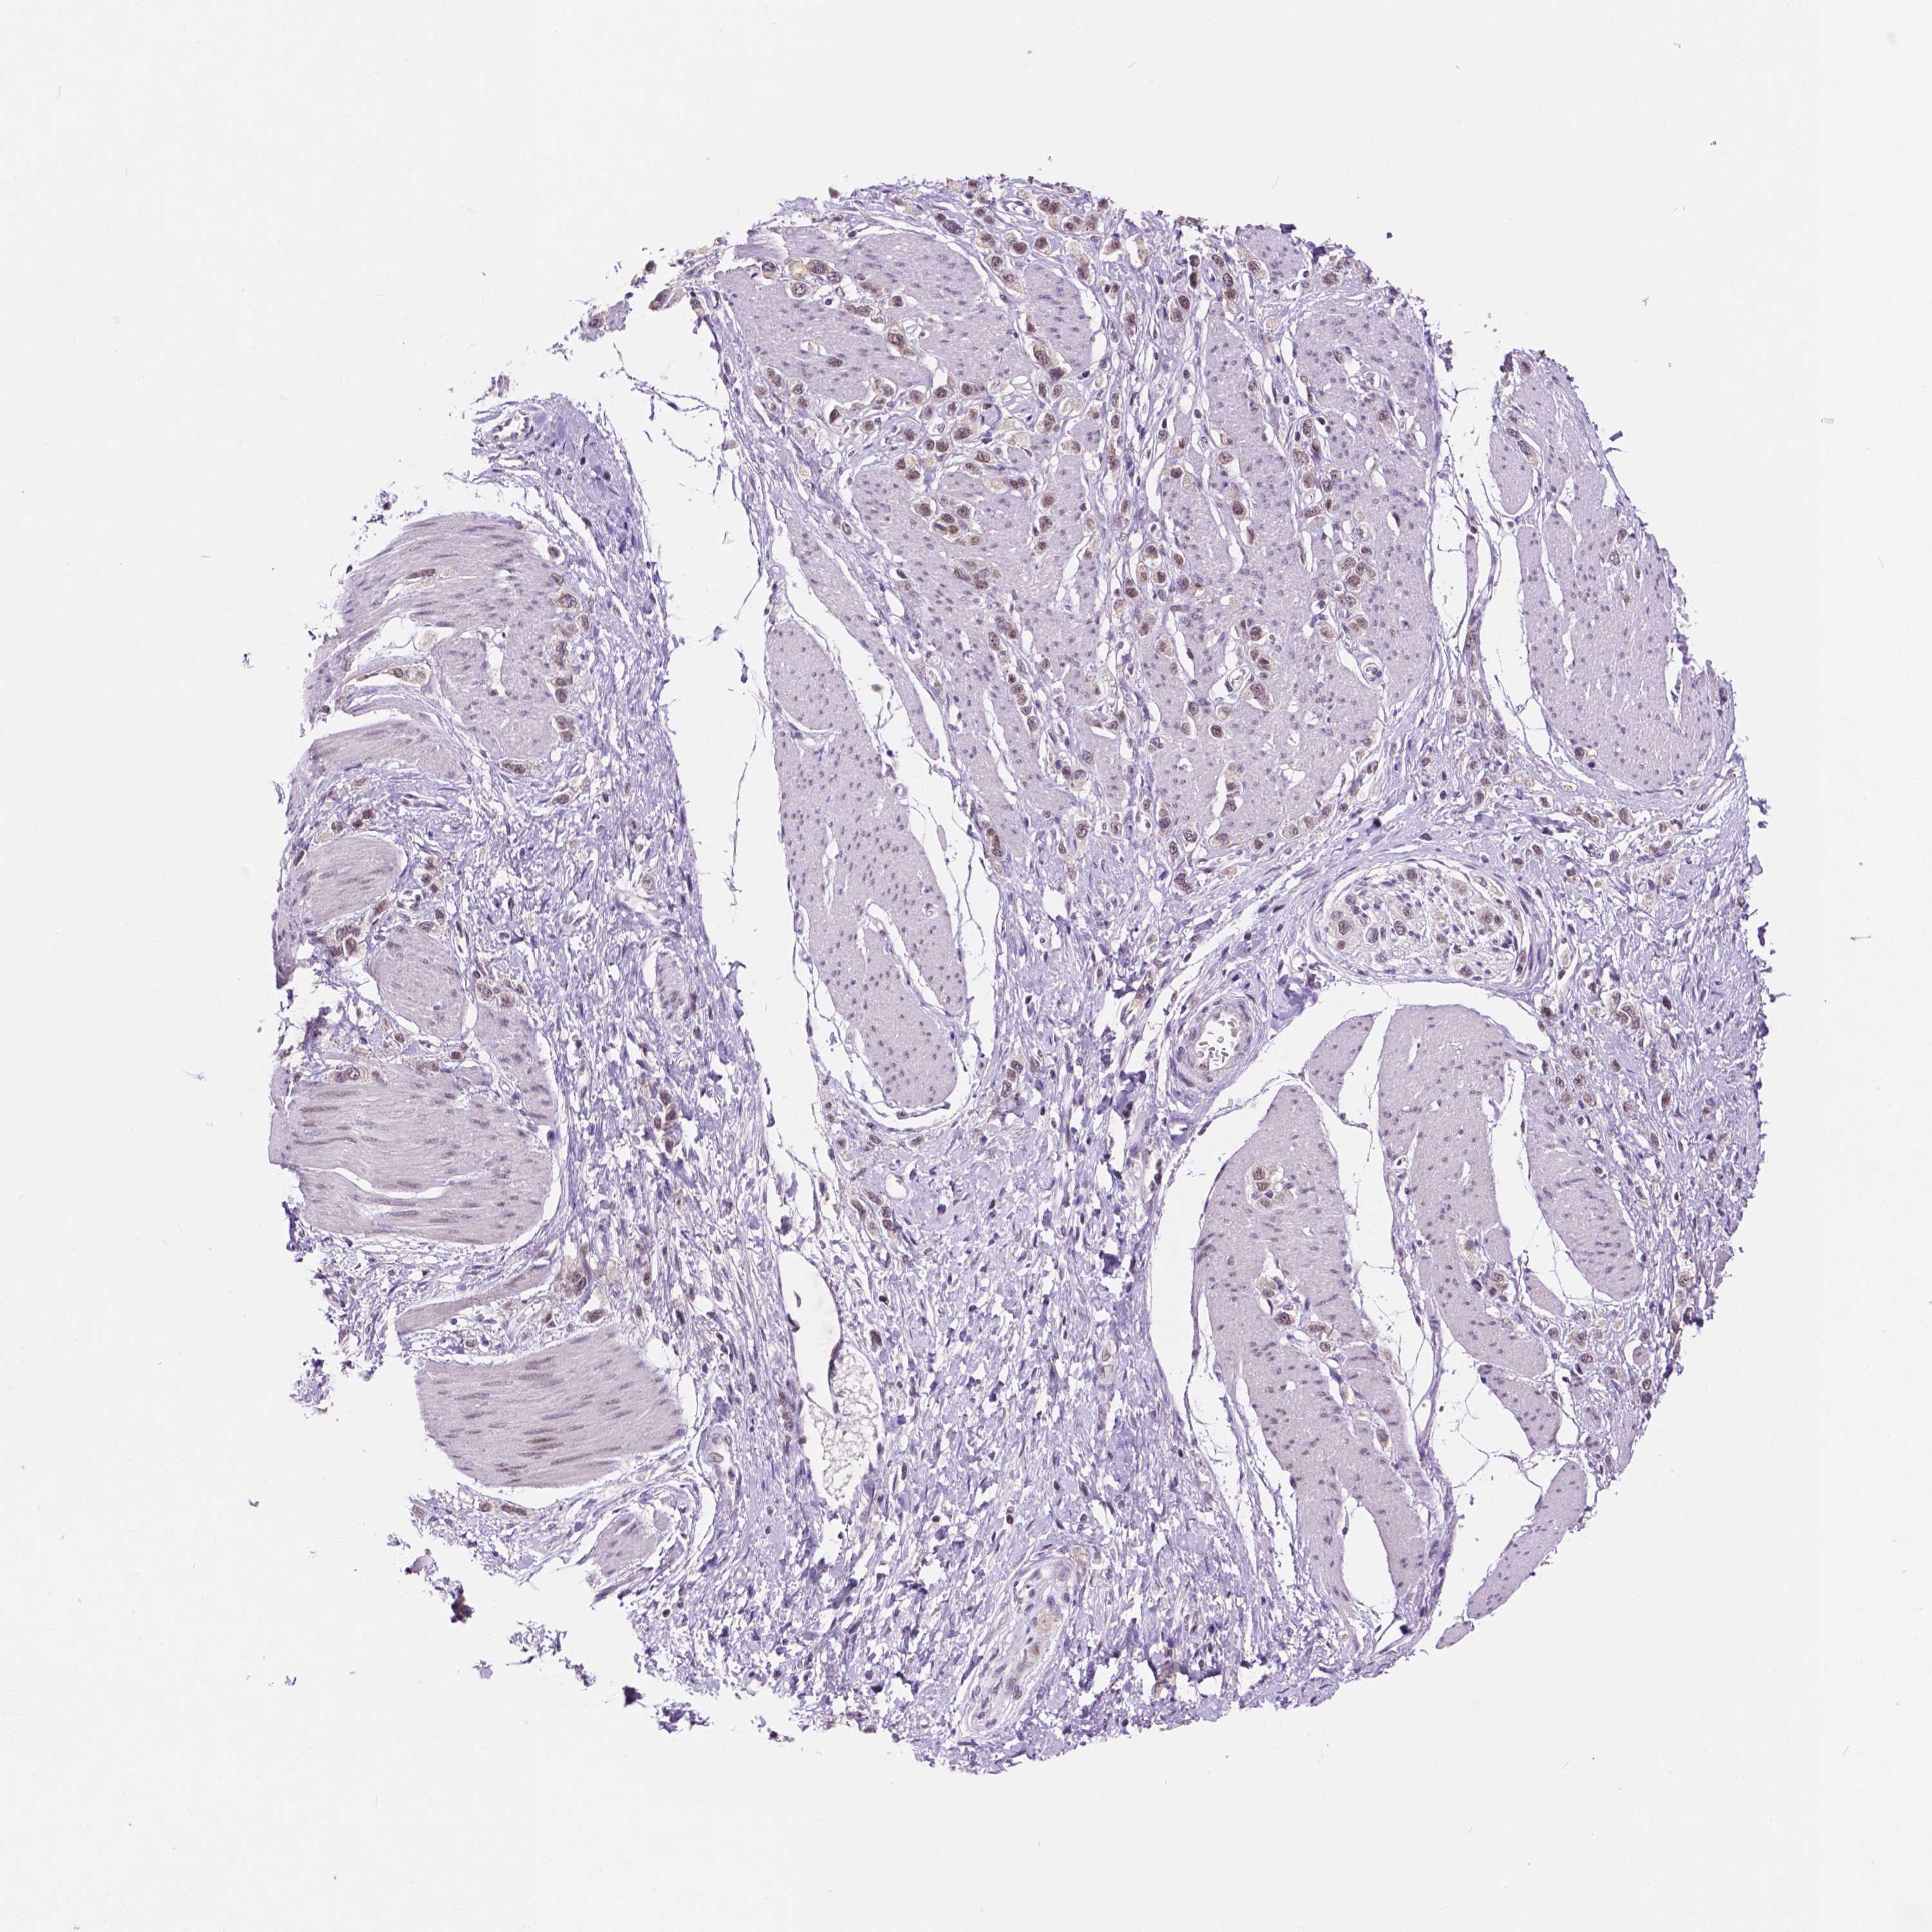

STOMACH CANCER - Protein expressioni

A mouse-over function shows sample information and annotation data. Click on an image to view it in a full screen mode. Samples can be filtered based on level of antibody staining by selecting one or several of the following categories: high, medium, low and not detected. The assay and annotation is described here.

Note that samples used for immunohistochemistry by the Human Protein Atlas do not correspond to samples in the TCGA dataset.

Antibody stainingi

Antibody staining in the annotated cell types in the current human tissue is reported as not detected, low, medium, or high, based on conventional immunohistochemistry profiling in selected tissues. This score is based on the combination of the staining intensity and fraction of stained cells.

Each image is clickable and will lead to virtual microscopy that enables deeper exploration of all samples and also displays staining intensity scores, fraction scores and subcellular localization as well as patient and tissue information for each sample.

Antibody HPA050288

Antibody HPA051168

Antibody CAB072830

Staining

High

Medium

Low

Not detected

Intensity

Strong

Moderate

Weak

Negative

Quantity

>75%

75%-25%

<25%

None

Location

Nuclear

Cytoplasmic/membranous

Cytoplasmic/membranous,nuclear

Adenocarcinoma, NOS